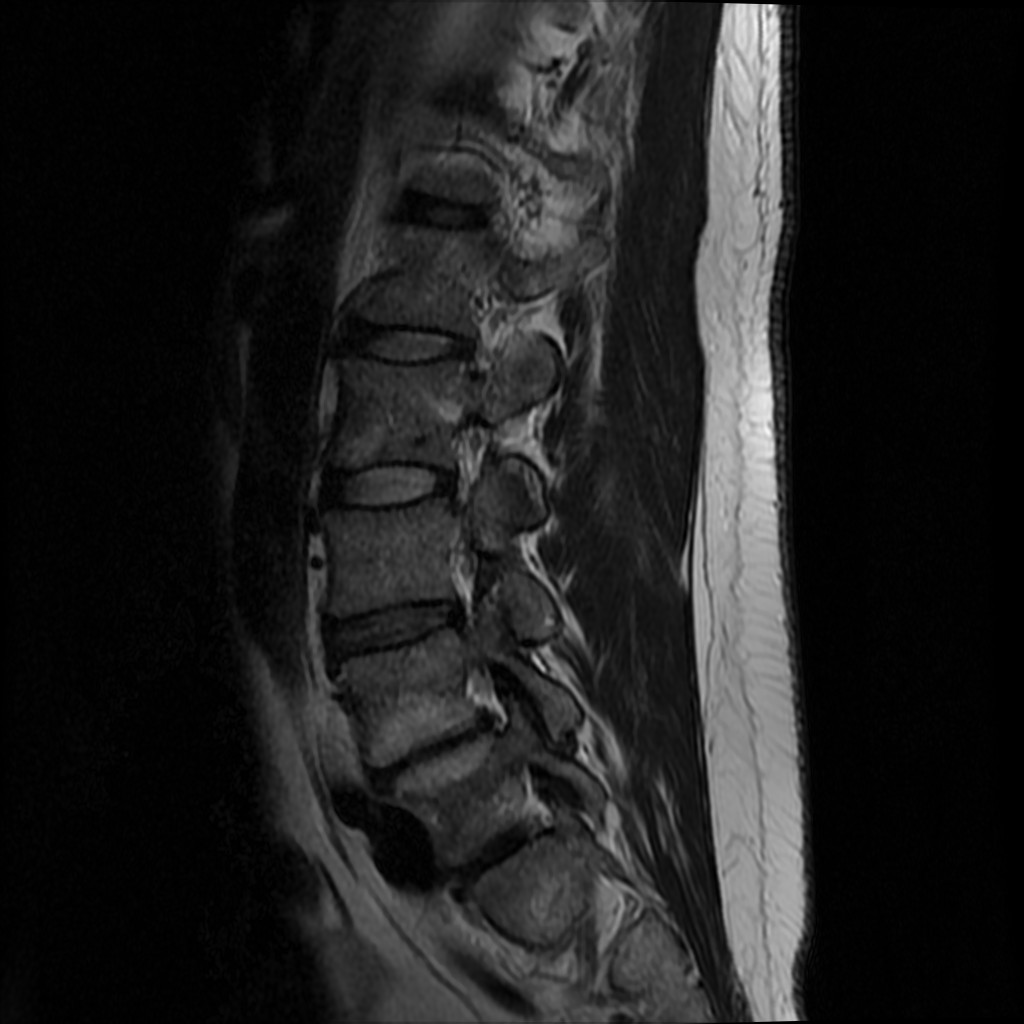

1. 🔴 FRATURA BURST L1 — SEQUELA SUBAGUDA/CRÓNICA (ACHADO PRINCIPAL): Corpo vertebral L1 com deformidade residual pós-fratura explosiva (burst). Perda de altura anterior e posterior do corpo vertebral com fragmentação óssea. Fragmento posterossuperior retropulsado comprometendo o canal raquídeo. Cifose segmentar pós-traumática ao nível da transição toracolombar. Em fase subaguda-crónica aos 3 meses — sem sinal STIR significativo de edema ósseo agudo. Margens irregulares e corticais perturbadas. Equivale a fractura AO Spine tipo A3/A4.

2. 🟠 COMPROMISSO DO CANAL MEDULAR EM L1: Estreitamento do diâmetro antero-posterior do canal raquídeo ao nível de L1, por fragmento ósseo retropulsado da parede posterior do corpo vertebral. Necessária avaliação do cone medular (extremidade inferior da medula espinhal em L1-L2) e das raízes da cauda equina. Sem evidência de lesão medular aguda neste exame tardio.

3. 🟡 CIFOSE PÓS-TRAUMÁTICA T12-L1: Deformidade em cifose segmentar ao nível da transição toracolombar secundária à fratura burst L1 com colapso do corpo vertebral. O ângulo de cifose local está aumentado. Esta deformidade sagital pode contribuir para dor crónica e progressão a longo prazo.

Fratura Burst L1: Deformidade residual com fragmentação da cortical do corpo vertebral

Cifose segmentar: Ângulo de cifose local aumentado em T12-L1

Canal medular: Estreitamento em L1 por fragmento retropulsado

→ Sagital T2: Melhor sequência para avaliar a deformidade vertebral, altura discal e sinal do cone medular

→ Sagital STIR: Sensível para edema ósseo residual — hipersinal discreto em L1 confirma fase subaguda-crónica

→ Sagital T1: Sinal heterogéneo em L1 — remodelação óssea em curso, sem colapso adicional

→ Axial T2: Permite quantificar o grau de compromisso do canal e avaliar as raízes da cauda equina